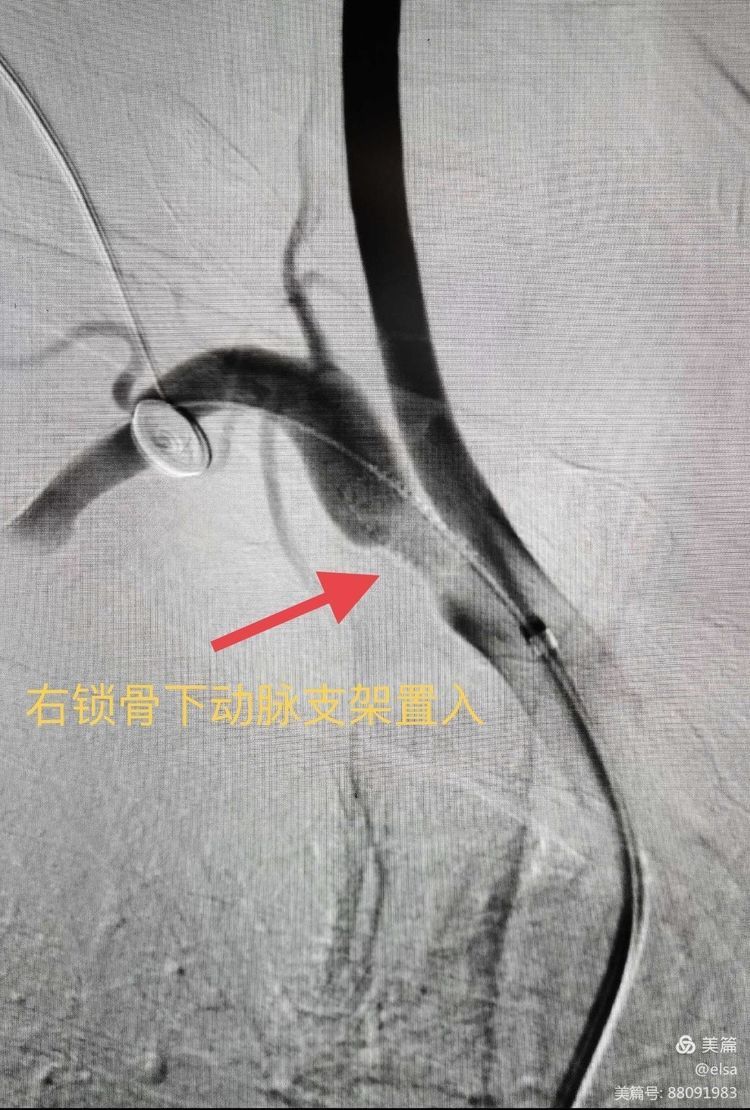

“今天我18岁啦!” 今天对于大多数人来说,只是一个普通的工作日,但是对于小明(化名)来说却是人生中最重要的一天。 小明是血管介入科的住院患者,来自甘肃省永... -